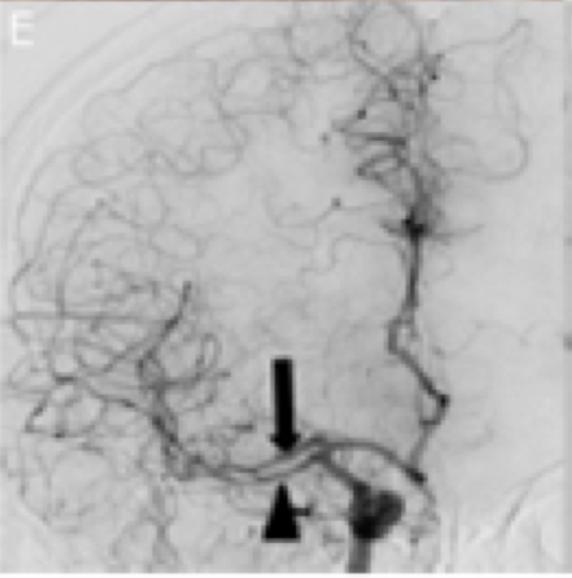

同样,对从颈内动脉终末端发出的AMCA分支重复上述过程。检查血管造影显示AMCA双支完全再通(图1E)。使用6×20 mm Mustang球囊扩张导管对动脉夹层段进行球囊血管成形术,右颈动脉球部可见明显的残余血栓(图1F)。

之所以有先后之分,是因为率先对发出豆纹动脉分支的血管进行再通对于取得良好预后更为关键。对两条分支进行单次抽吸后最终实现了完全再通(mTICI评分:3级)。